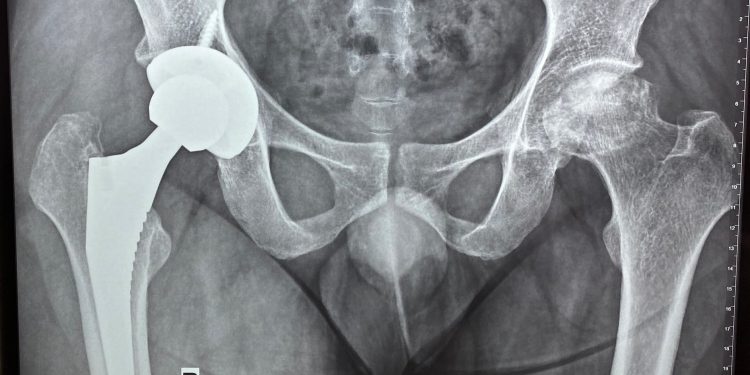

Bệnh viện Đa khoa tỉnh Khánh Hòa đã phẫu thuật thành công nhiều ca thay khớp nhân tạo. Ngoài các bệnh nhân cao tuổi, đã từng thay cho bệnh nhân 104 tuổi, sau chấn thương té ngã được thay khớp háng để phục hồi chức năng vận động trong sinh hoạt. Trung tâm Chấn thương Chỉnh hình – Bỏng (TT CTCH-B) đã thay khớp háng thành công cho các bệnh nhân trẻ tuổi bị hoại tử vô khuẩn chỏm xương đùi.

Vừa qua, bệnh nhân Trần Ngọc P. sinh năm 1988, tại Nha Trang. Cách đây 6 tháng đã thay khớp háng phải tại BVĐK tỉnh Khánh Hòa. Ngày 22/3/2021 bệnh nhân được phẫu thuật thay khớp háng trái toàn phần không xi măng thành công.

Ngày 24/3/2021, ê kíp phẫu thuật gồm BSCKII. Phan Hữu Chính, BSCKI. Nguyễn Ngọc Nghĩa và BSCKI. Hoàng Trung Thông của TT CTCH-B đã thành công ca thay khớp háng trái toàn phần không xi măng cho bệnh nhân Đinh Xuân T. 39 tuổi được chẩn đoán Hoại tử chỏm xương đùi 2 bên.